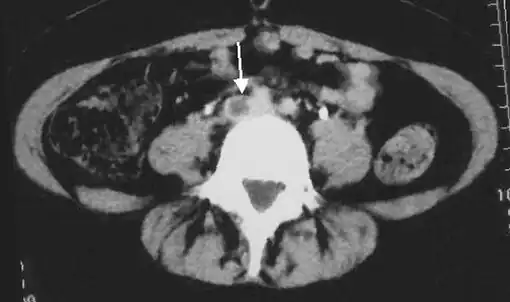

CT scan venography, MRI venography, or a non-contrast MRI are also diagnostic possibilities.[120] The gold standard for judging imaging methods is contrast venography, which involves injecting a peripheral vein of the affected limb with a contrast agent and taking X-rays, to reveal whether the venous supply has been obstructed. Because of its cost, invasiveness, availability, and other limitations, this test is rarely performed.[39]